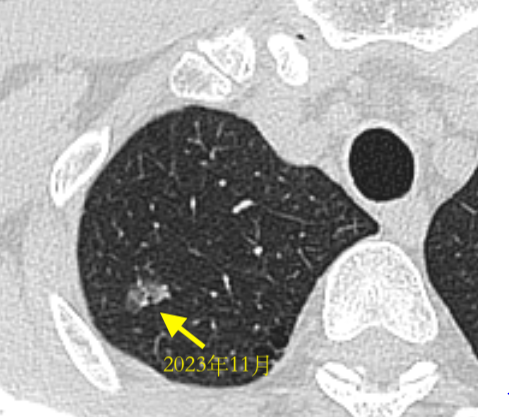

1年半后手术前复查,变化不大

5、血管集束征:该患者增强CT可见结节内血管集束征,且血管形态似有扭曲、牵拉

通过以上几点临床就基本可以判定这个结节是早期肺癌,至少微浸润以上,很可能已经达到了浸润,但因为已观察1年半无明显变化,判断侵袭性不高,所以我们为患者制定了胸腔镜右肺上叶尖段切除术,就是切除1个肺叶的1/3,既达到了根治性切除的目的,又最大限度的保留了肺功能。